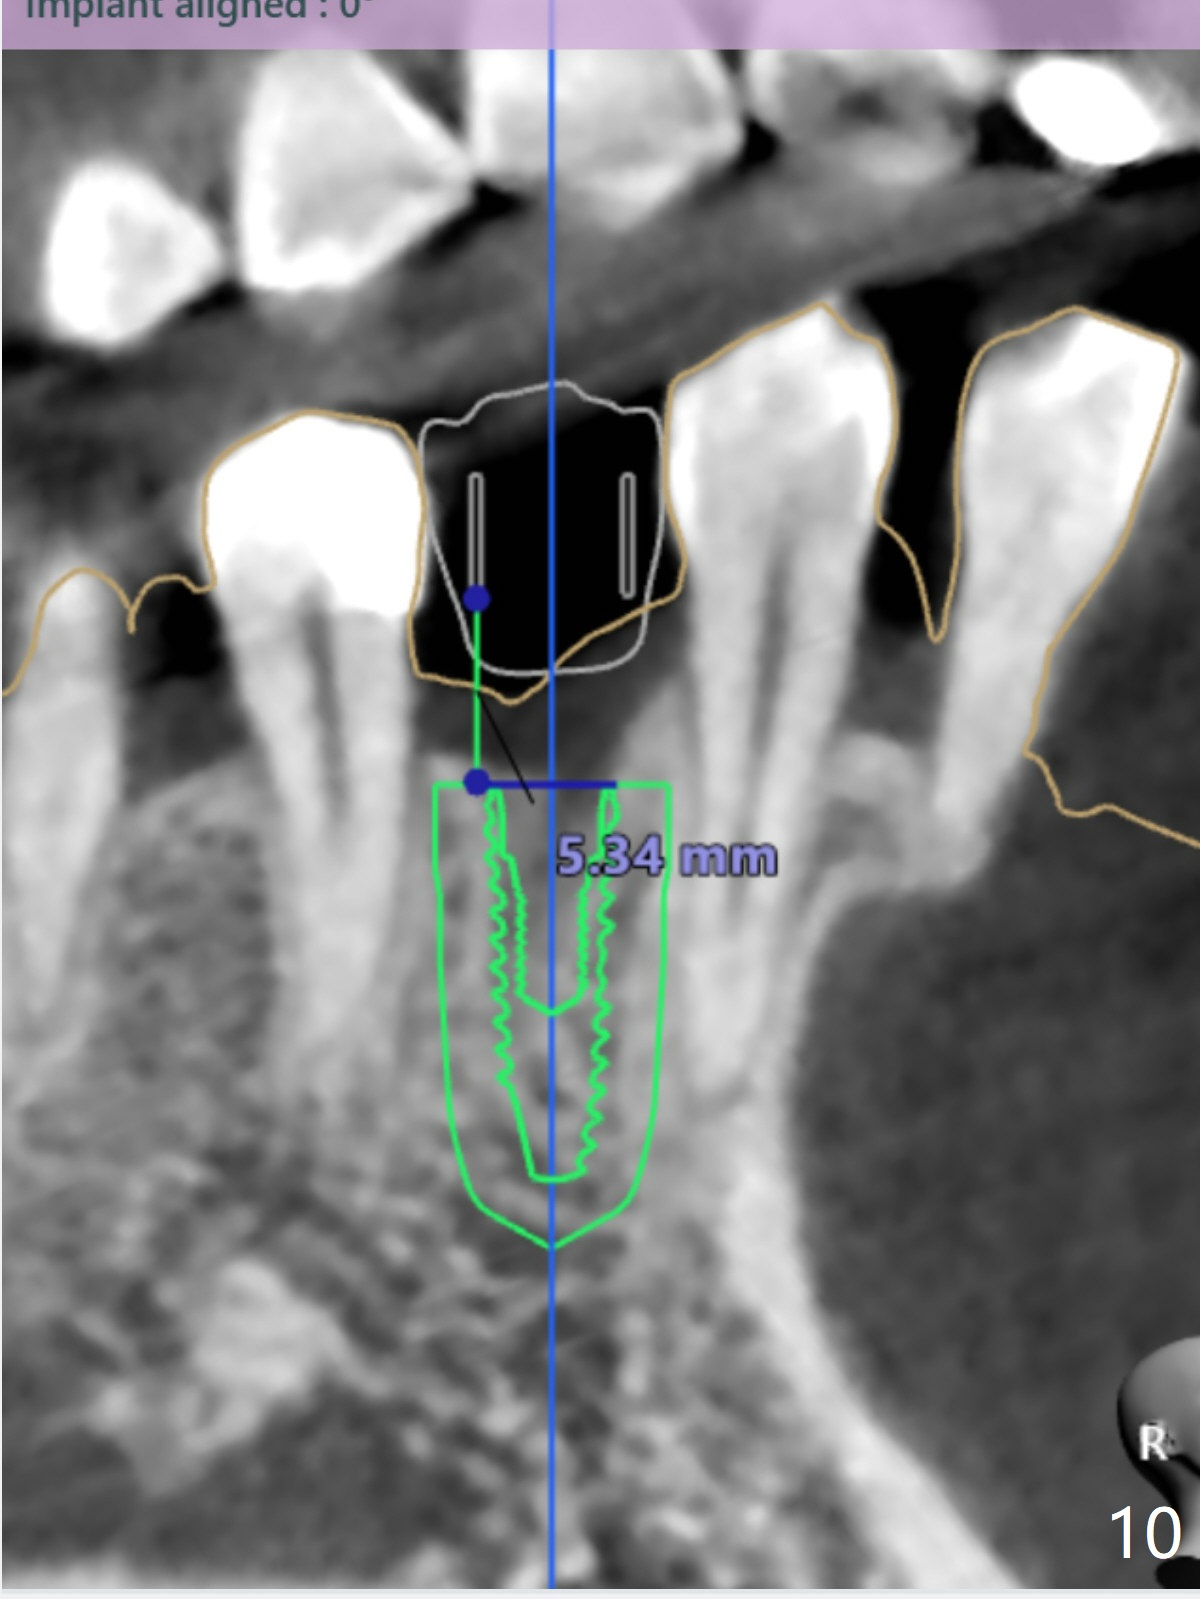

For buccal concavity at #28 to be fixed with bone expansion (DIO Bone Expanders Kit), surgical guide has modification (Fig.5,8).